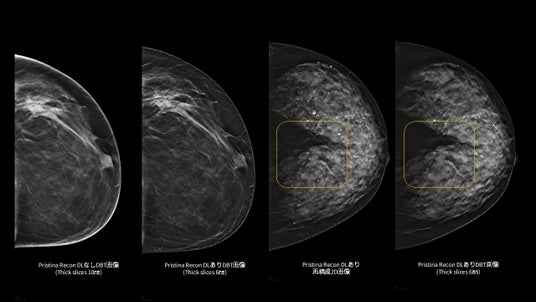

「Pristina Recon DL」¹は、MRIの画像再構成にディープラーニングを適用したGEヘルスケア独自のAIR(TM) Recon DL技術を基盤としています。本アプリケーションで、乳房のデジタルブレストトモシンセシス (DBT/3Dマンモグラフィ) 技術の更なる可能性を追求し、低線量での撮影でも、より高画質な画像の提供を目指します。また、アーチファクト(虚像)や視覚的ノイズの低減を図り、微細構造の視認性の向上にも寄与します。²,³

「Pristina Recon DL」は、ディープラーニングと逐次近似再構成技術を活用した、デジタルブレストトモシンセシス(DBT/3Dマンモグラフィ)向けの画像再構成技術です。また、被ばく線量を増加させることなく、高画質で安定したDBT/3Dマンモグラフィ画像の提供を目指します。

さらに、ディープラーニングを用いた高度な画像再構成技術により、アーチファクト(虚像)や視覚的ノイズを低減し、微細構造の視認性を向上させます。これにより、DBT/3Dマンモグラフィおよび再構成2D画像の双方において、読影に必要な情報をより明確に可視化し、診断を支援する読影環境の向上に貢献します。